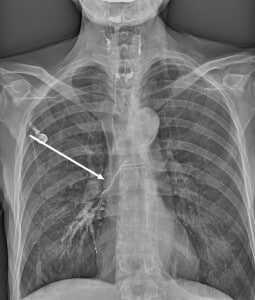

- Обязательным является проведение рентгенографии и рентгеноскопии пищевода с водорастворимым контрастным веществом (барий использовать не рекомендуется, рисунок 1, 2).

Пищеводно-респираторный свищ при рентгенографии/рентгеноскопии пищевода